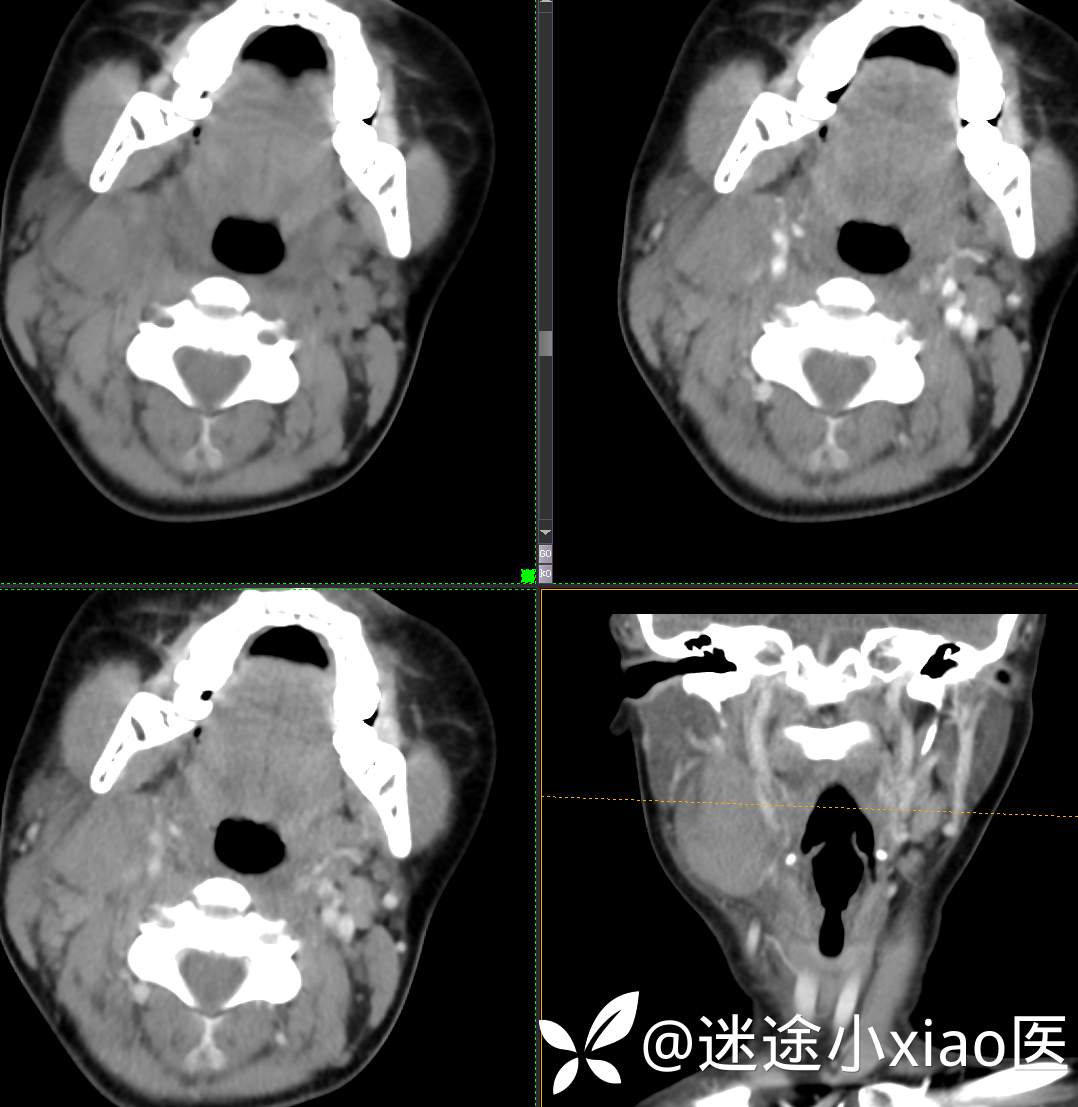

头颈组16:青少年女性,发现右颈部肿物半月余,感染?肿瘤?

主 诉:发现颈部肿物半月余

现病史:患者半月余前无明显诱因下发现右颈部肿物,大小4.2*2.1cm,局部无红肿,皮温正常,有压痛,感头晕头痛,无其他不适。查甲状腺及颈部淋巴结B超提示:双侧甲状腺多发结节;右侧多发肿大淋巴结。初步诊断为“淋巴炎”,予“头孢类”抗生素抗感染治疗12天(具体药物不详),自觉肿块胀痛缓解,头晕头痛症状仍存。